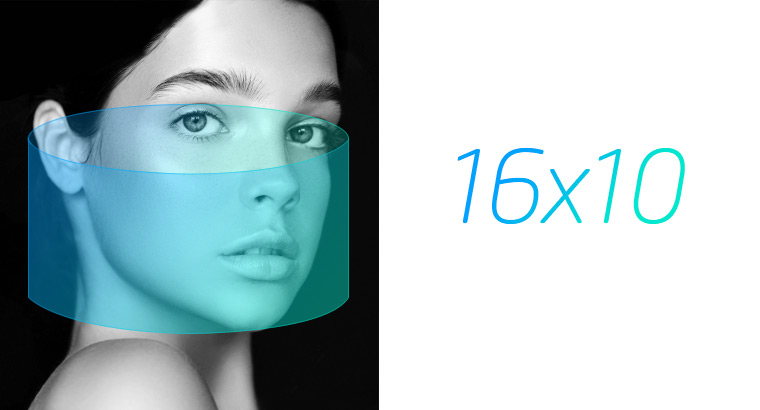

See where you focus

Light guided free FOV